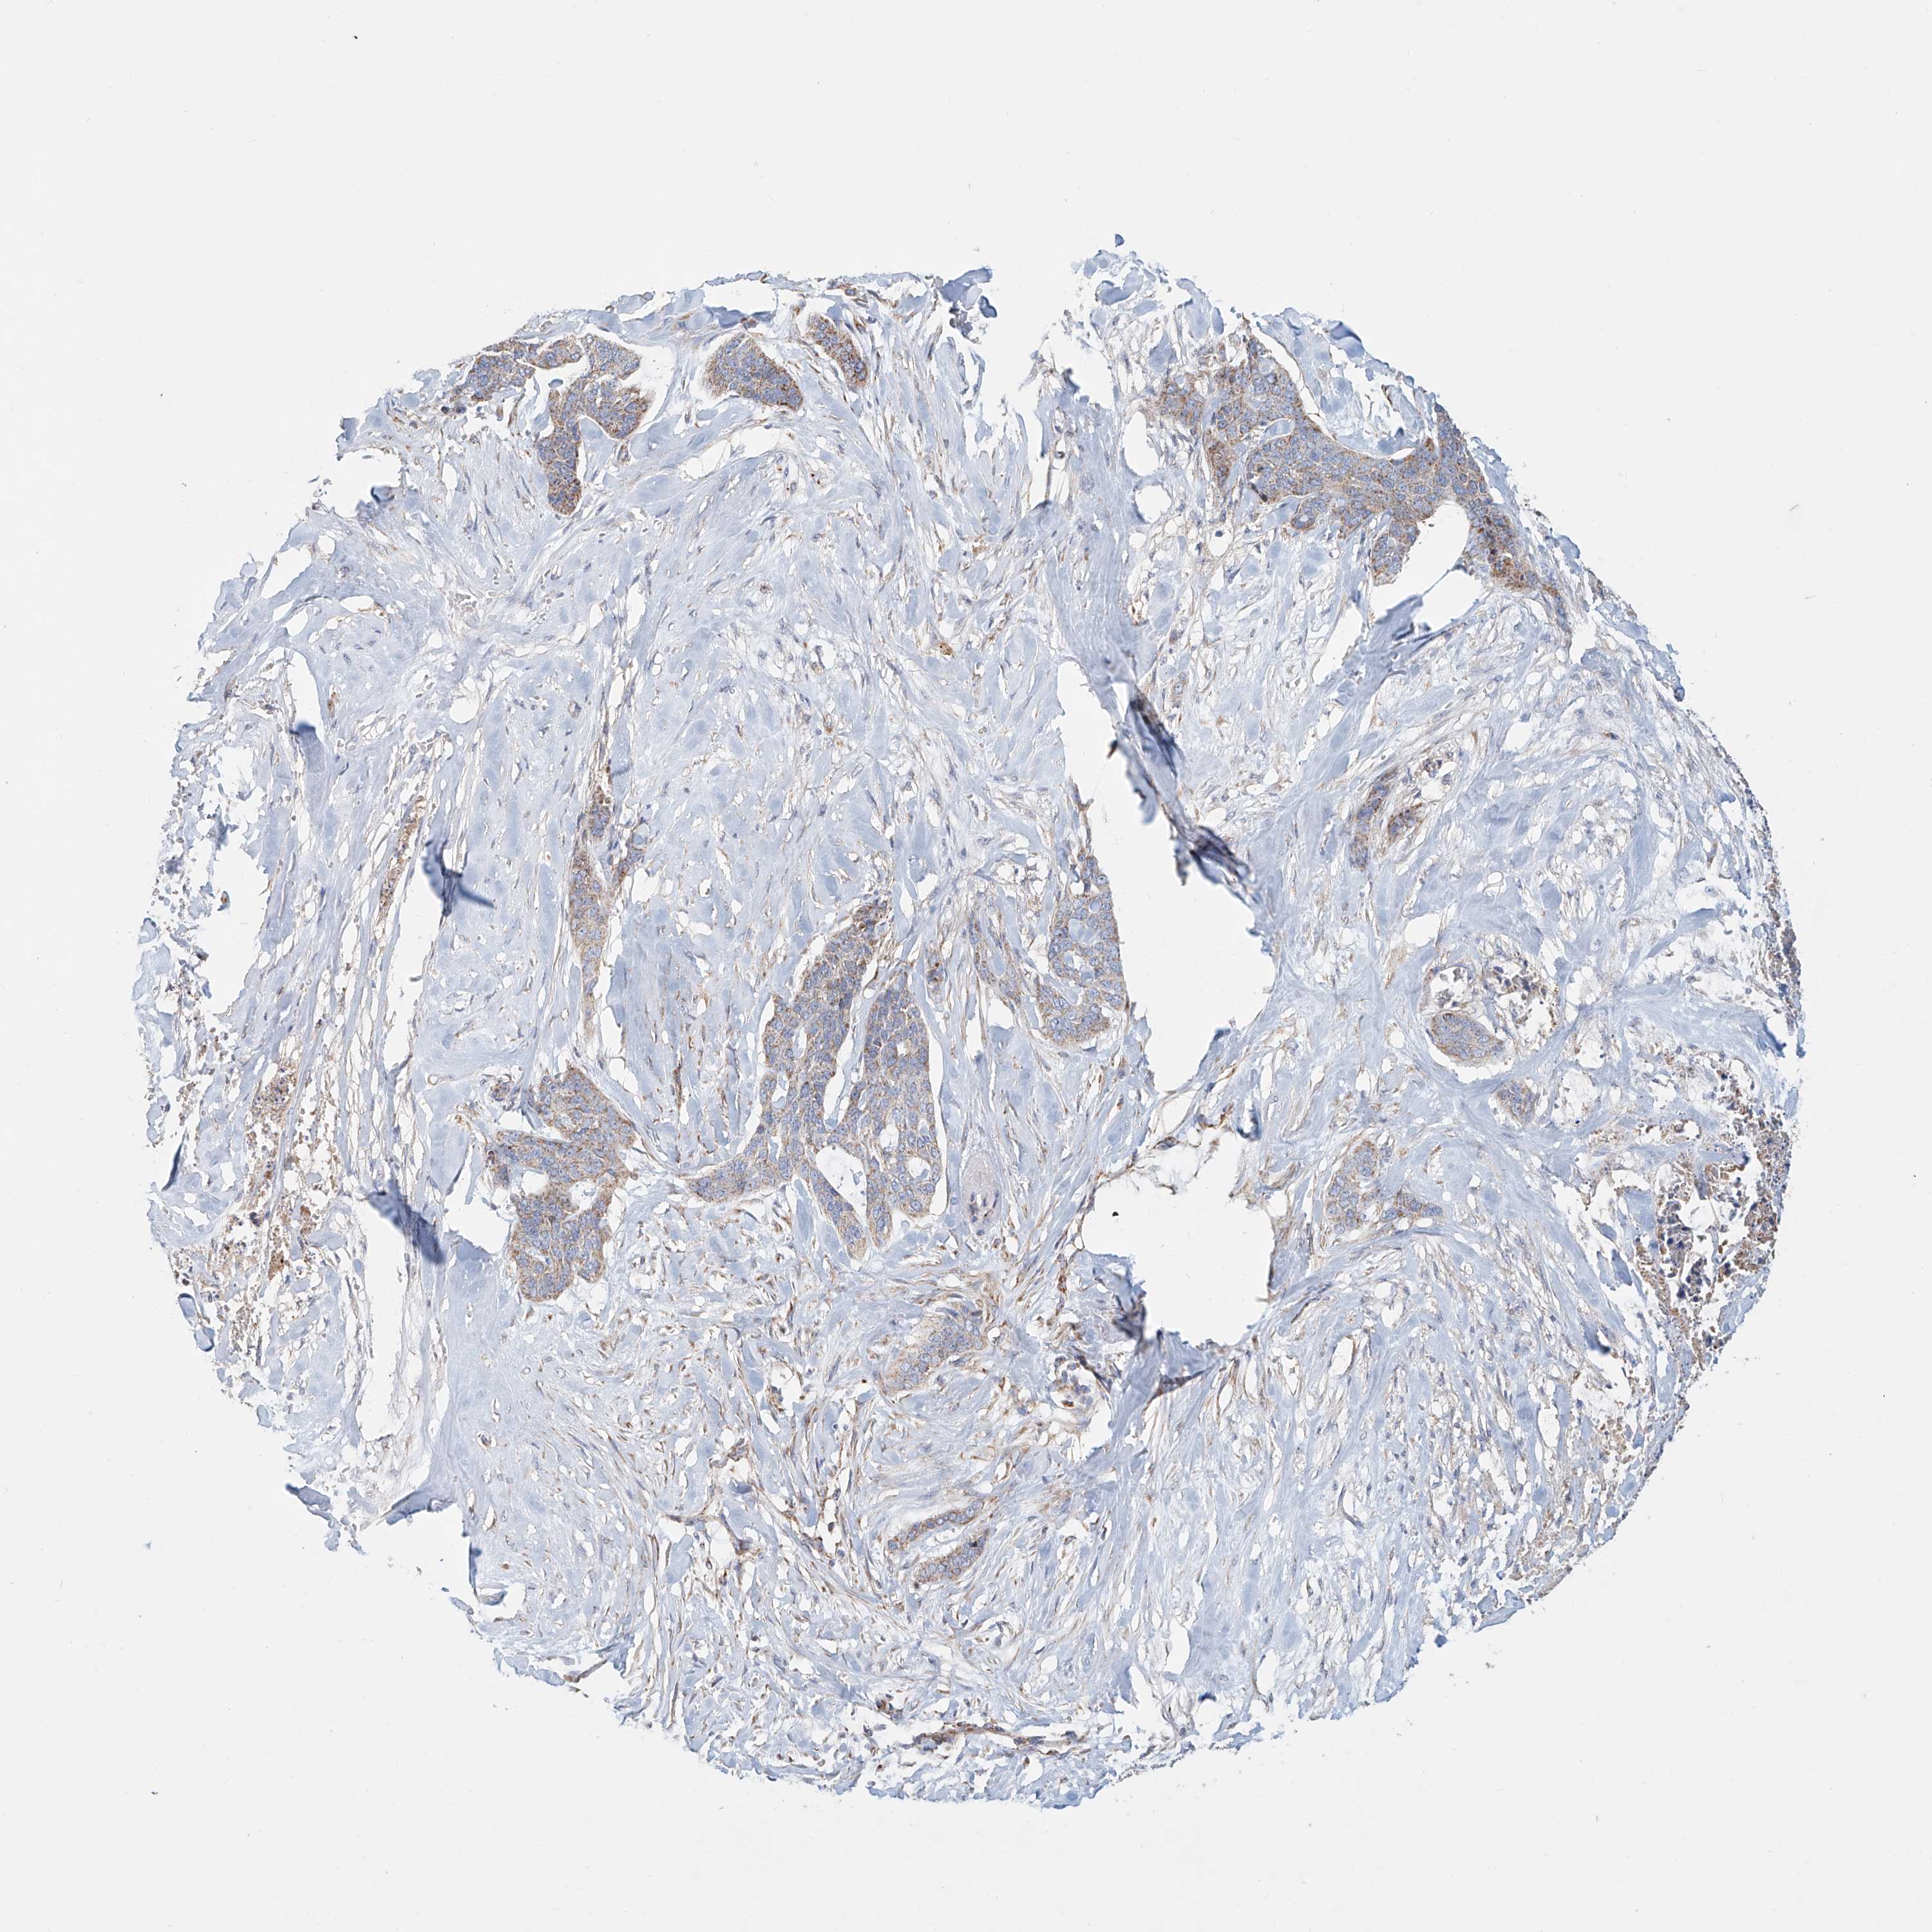

SKIN CANCER - Protein expressioni

A mouse-over function shows sample information and annotation data. Click on an image to view it in a full screen mode. Samples can be filtered based on level of antibody staining by selecting one or several of the following categories: high, medium, low and not detected. The assay and annotation is described here.

Antibody stainingi

Antibody staining in the annotated cell types in the current human tissue is reported as not detected, low, medium, or high, based on conventional immunohistochemistry profiling in selected tissues. This score is based on the combination of the staining intensity and fraction of stained cells.

Each image is clickable and will lead to virtual microscopy that enables deeper exploration of all samples and also displays staining intensity scores, fraction scores and subcellular localization as well as patient and tissue information for each sample.

Antibody HPA008455

Antibody HPA031125

Antibody CAB002781

Antibody CAB068195

Squamous cell carcinoma, NOS

Squamous cell carcinoma, metastatic, NOS

Basal cell carcinoma

Papilloma, NOS